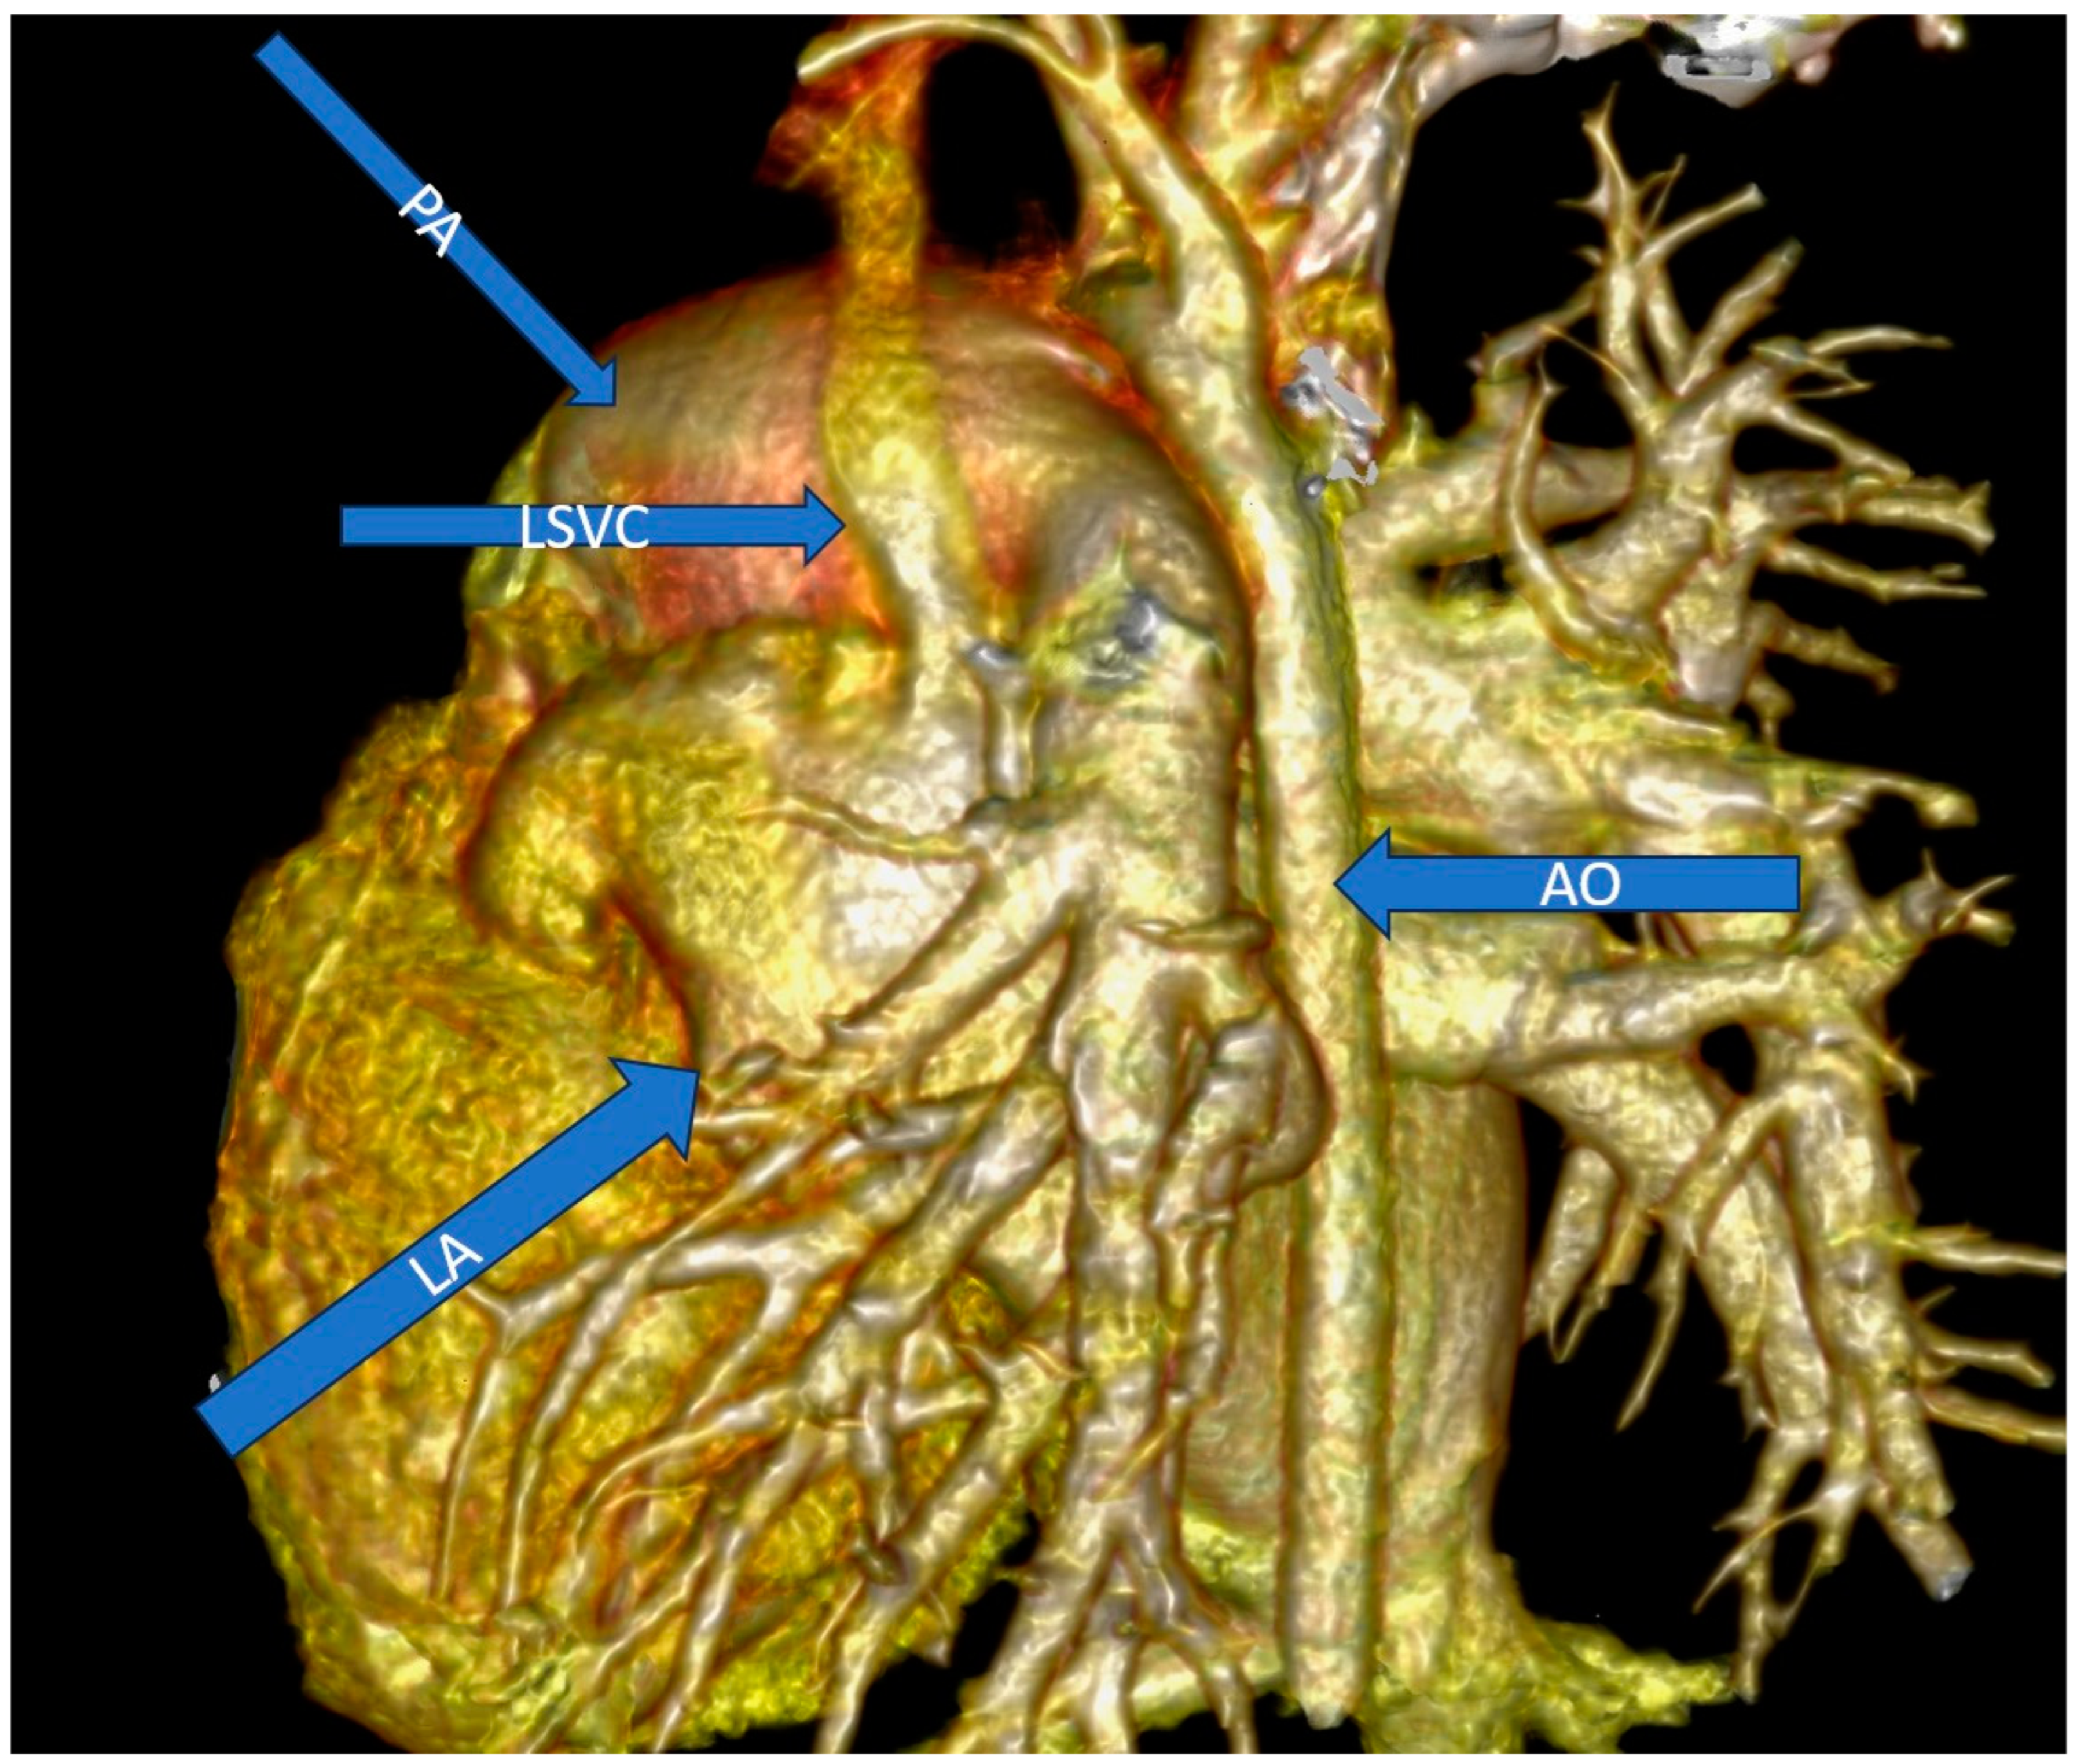

2.2. Diagnostic Assessment